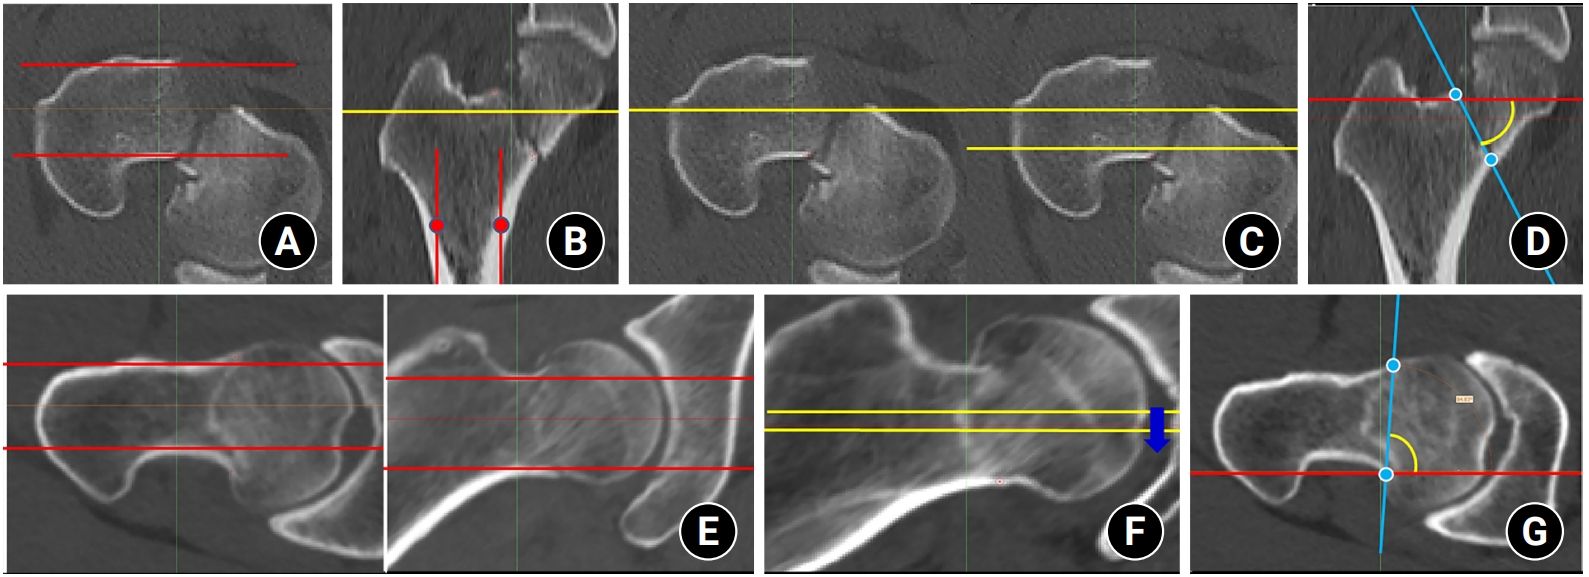

Data sources and measurement

Fig. 2.

To make consistent measurements and eliminate projection error, after the computed tomography scan plane was reformatted to an axial plane parallel to the femoral neck axis, red lines were placed anterior and posterior to the neck cortex in the axial (A) and coronal (B) planes. The yellow lines were placed in the centerline and posterior cortex (C). Then, (D) the coronal Pauwels angle (PA) was measured between the red line (ground line) and the blue line (reformatted fracture angle) in three consecutive images of the coronal plane. (E) The red line marked the anterior and posterior cortex in the axial and coronal planes. (F) The yellow lines were placed along the centerline of the neck, and three consecutive images of the axial plane were chosen. Then, (G) The axial PA was measured between the red line (ground line) and the blue line (reformatted fracture angle).

Fig. 2. To make consistent measurements and eliminate projection error, after the computed tomography scan plane was reformatted to an axial plane parallel to the femoral neck axis, red lines were placed anterior and posterior to the neck cortex in the axial (A) and coronal (B) planes. The yellow lines were placed in the centerline and posterior cortex (C). Then, (D) the coronal Pauwels angle (PA) was measured between the red line (ground line) and the blue line (reformatted fracture angle) in three consecutive images of the coronal plane. (E) The red line marked the anterior and posterior cortex in the axial and coronal planes. (F) The yellow lines were placed along the centerline of the neck, and three consecutive images of the axial plane were chosen. Then, (G) The axial PA was measured between the red line (ground line) and the blue line (reformatted fracture angle).